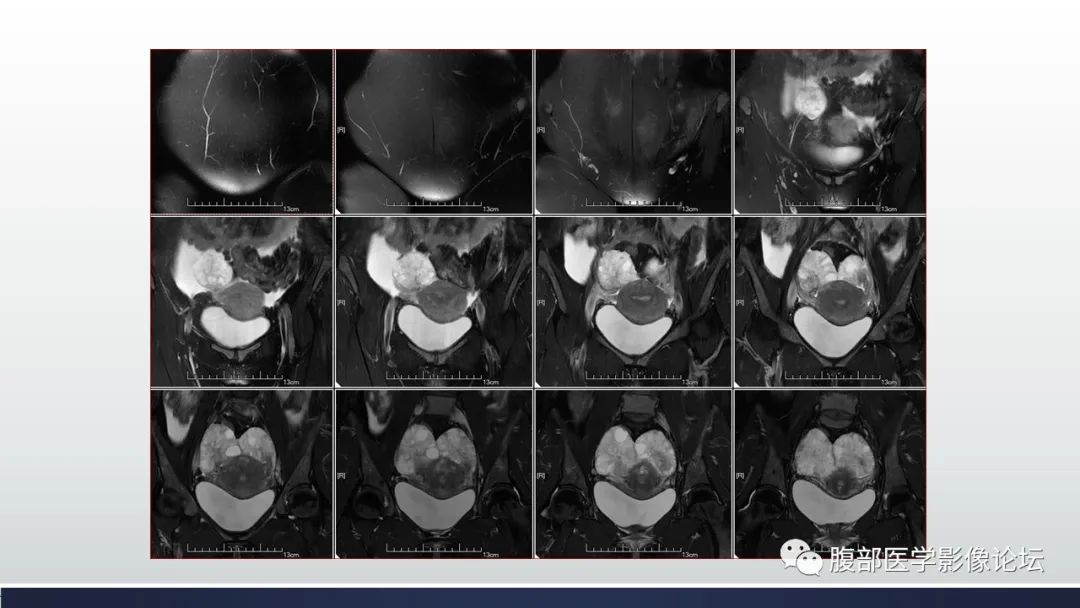

【病例】子宫内膜透明细胞癌1例MR-1

【病例】子宫内膜透明细胞癌1例MR-2

【病例】子宫内膜透明细胞癌1例MR-3

【病例】子宫内膜透明细胞癌1例MR-4